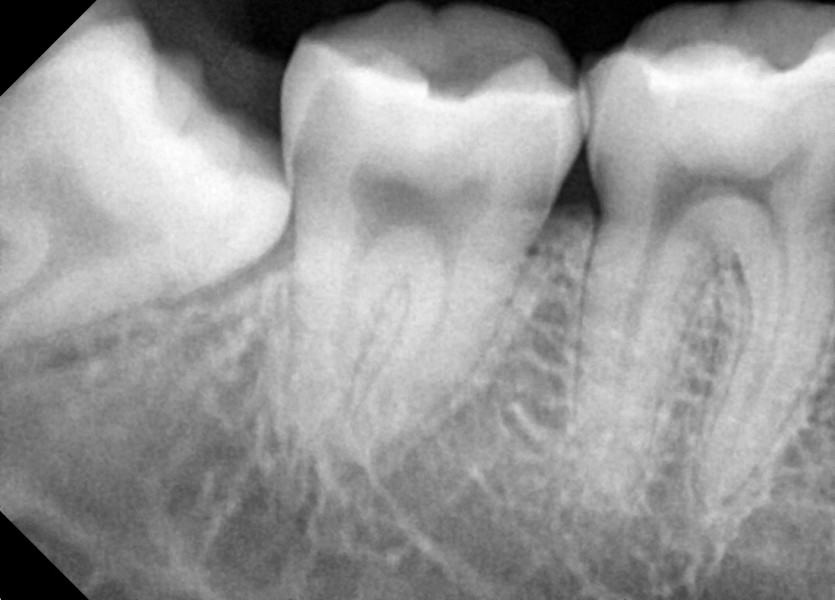

#38,48 사랑니 발치

구강 외과 전문의가 당일 발치했습니다.